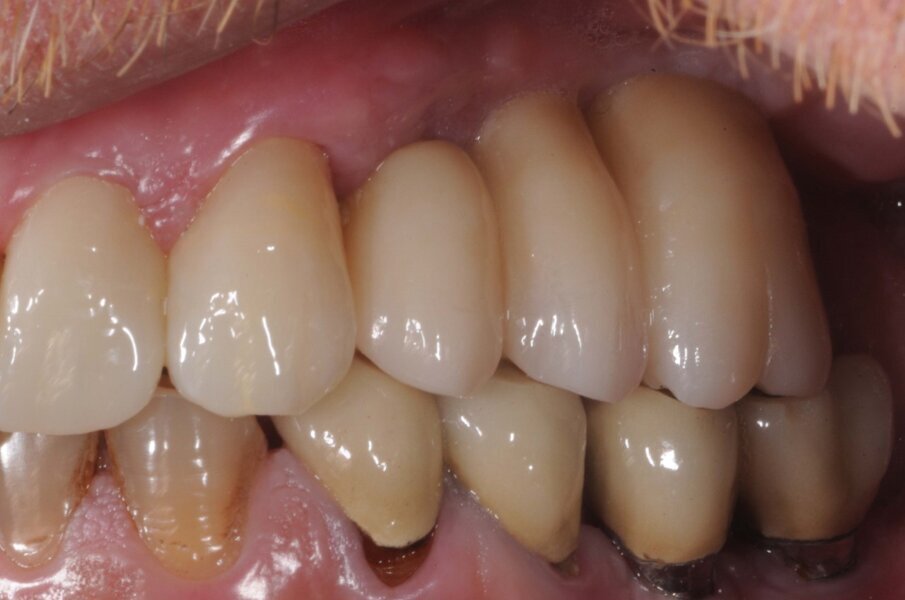

Dopo tre settimane è stata presa l’impronta finale con la tecnica del cucchiaio aperto, eseguita la registrazione occlusale e dopo tre settimane è stato consegnato un ponte in zirconio fresato ritenuto da viti e con successivo controllo radiografico (Figg. 8, 9).

Ad un anno di distanza dalla consegna è stato eseguito un controllo radiografico (Fig. 10). Il dettaglio ingrandito della radiografia periapicale evidenziava una maturazione dell’osso attorno all’apice dell’impianto all’interno del seno mascellare. Clinicamente il tessuto gengivale appariva sano e senza alterazioni.